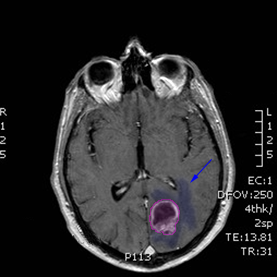

Περιγραφή Η επέμβαση μπορεί να γίνει υπό τοπική ή, συχνότερα, γενική αναισθησία. Υπάρχουν 2 τρόποι να πραγματοποιηθεί η εντόπιση της εξεργασίας: ο πρώτος είναι με τη βοήθεια στεροτακτικού πλαισίου από τιτάνιο το οποίο στερεώνεται στο κρανίο του ασθενούς με ειδικές βίδες και ο δεύτερος με την βοήθεια νευροπλοήγησης, χωρίς εξωτερικά εντοπιστικά βοηθήματα. Και στις 2 περιπτώσεις πραγματοποιείται μια μαγνητική τομογραφία εγκεφάλου προεγχειρητικά για τον σχεδιασμό της επέμβασης (σημείο εισόδου και τροχιά της βελόνης). Η λήψη της βιοψίας γίνεται μέσω κρανιοανάτρησης (διάνοιξη μικρής οπής στο κρανίο) και με τη βοήθεια ειδικής βελόνης με κοπτική θαλάμη η οποία εισέρχεται στον εγκέφαλο προκειμένου να ληφθούν τεμάχια της εξεργασίας. Από την ίδια βελόνη μπορεί να αφαιρεθεί υγρό για κυτταρολογική εξέταση ή καλλιέργεια. |

Όγκος εγκεφάλου με περιβάλλον οίδημα. |